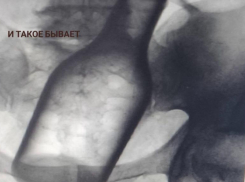

Здоровье Монета, проволока, бутылка: что извлекали из ставропольских пациентов в 2025 году

02.02.2026

И такое бывает